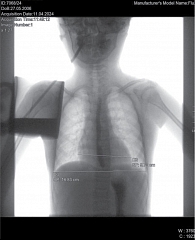

Рис. 4. Рентгенологическое исследование органов грудной клетки. Сердечно-грудной индекс – 0,48 (горизонтальный размер тени сердца – 10,75 см)

Рентген органов грудной клетки: отмечен повышенный горизонтальный размер тени сердца – 10,75 см. Сердечно-грудной индекс – 0,48 – повышен и характерен для начальной стадии дилатационной кардиомиопатии (рис. 4).

Рентген органов грудной клетки: отмечается повышенный горизонтальный размер тени сердца – 9,8 см. Сердечно-грудной индекс – 0,50 (рис. 6).